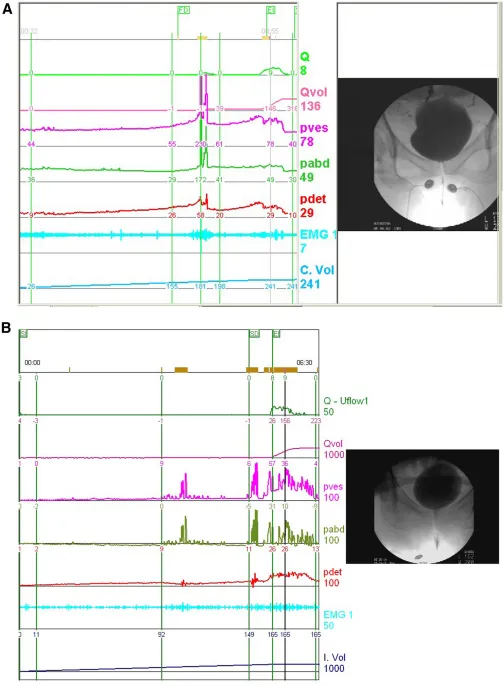

The field demands integration of urodynamic parameters (detrusor pressure >15 cmH₂O, maximum flow rate >15 mL/sec, post-void residual <100 mL), imaging findings (bladder neck descent >10mm, cervical descent >6cm below ischial spines), and functional assessments (Pelvic Floor Distress Inventory scores >95, quality of life impact scores >33).

💡 Master This: Detrusor overactivity shows involuntary contractions >15 cmH₂O during filling phase, while sensory urgency demonstrates normal detrusor function with increased sensation. Neurogenic patterns exhibit detrusor-sphincter dyssynergia with elevated post-void residuals >100 mL. Treatment success rates: detrusor overactivity 75%, sensory urgency 60%, neurogenic 45%.